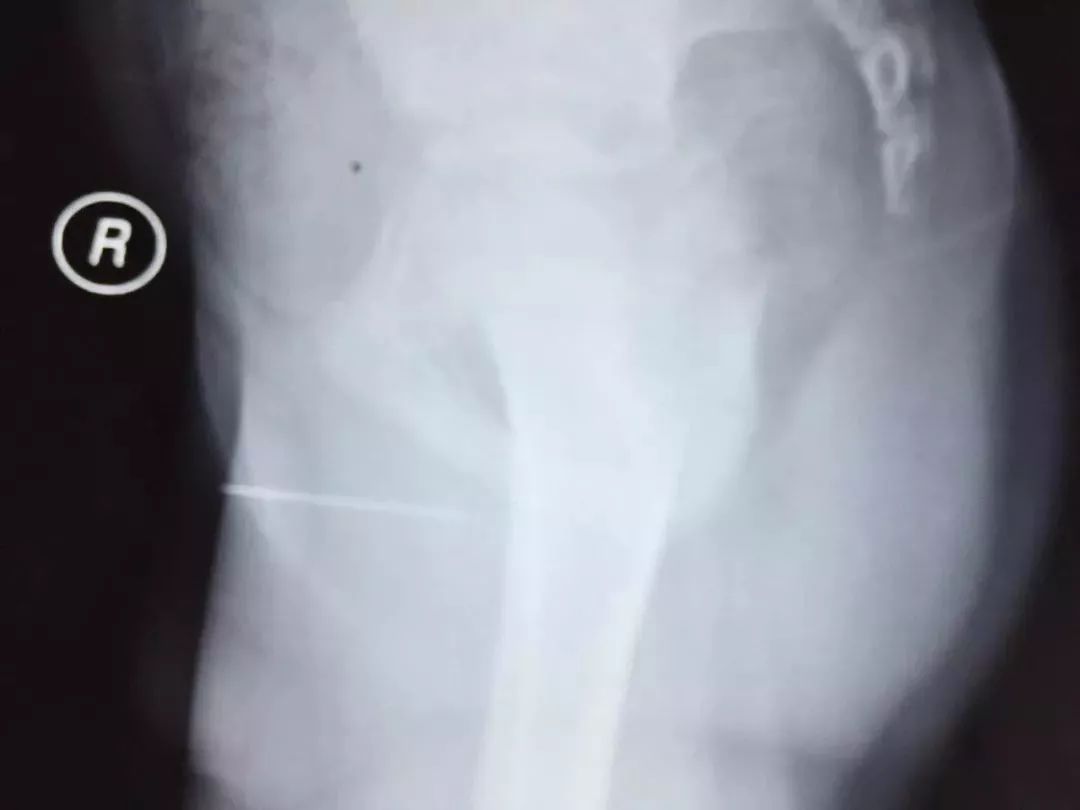

家人带着小刘到我市某医院拍摄X光片后发现,这根没入小刘尿道的缝衣针竟然长达4.2厘米。同时,小刘除了尿道疼痛外,还出现尿痛、少许血尿等症状。随后,小刘被转至北海市人民医院泌尿外科住院治疗。

据北海市人民医院泌尿外科主任陈奎介绍,小刘入院以来精神状态良好,根据检查结果,医生初步诊断为尿道内异物,且异物两端均已扎入尿道软组织。为让尽量减少孩子的痛苦,医生决定通过微创手术为小刘取出异物。

“我们取出异物后发现,这是一根有针眼的缝衣针,长度约4.2厘米,针体已经生锈。手术非常顺利,在输尿管镜的辅助下,我们用异物钳从尿道将异物取出,手术中没有明显出血。”陈奎说,所幸男孩及时将情况告诉家人,并及时得到规范治疗,万一拖久了,缝衣针将造成尿道化脓感染,情况严重的话,还需要切开尿道取出缝衣针。